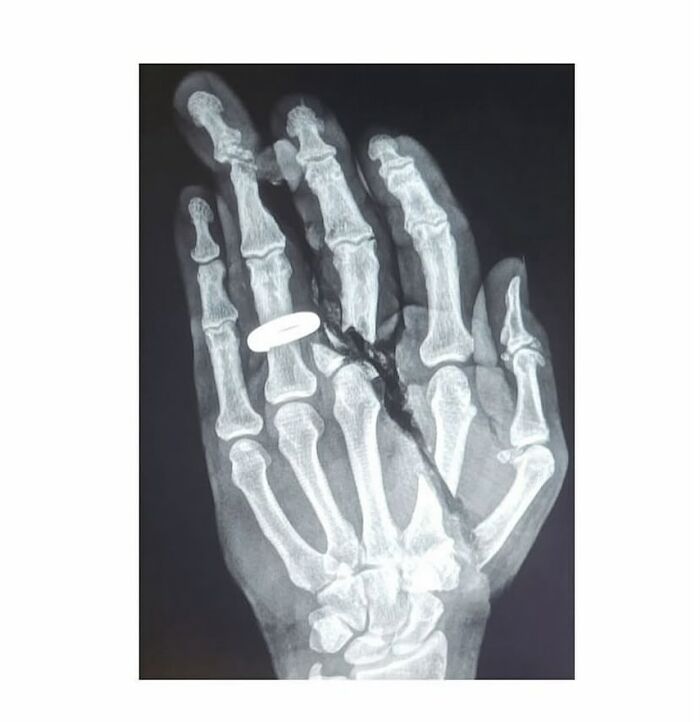

La radiografía simple de la articulación de la muñeca muestra polidactilia con duplicación del cúbito, duplicación de la cara cubital de los huesos del carpo, metacarpianos y falanges, ausencia de radio y ausencia del pulgar. Se observan ocho dedos trifalángicos. La falange media del dedo índice medial es hipoplásica.